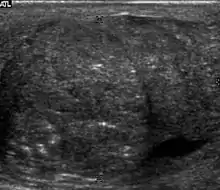

Fibrotic striations

Fibrotic striations.

A striated pattern of the testicle, radiating from its mediastinum, does not have clinical importance unless there are alarming symptoms or abnormal signal on Doppler ultrasonography.[3] It is presumed to represent fibrosis.[3]